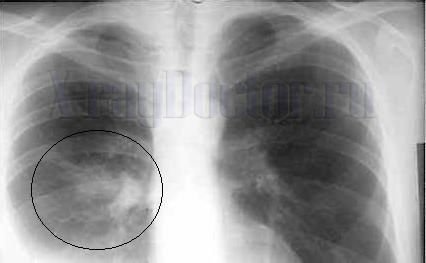

Из-за анатомических особенностей грудной клетки при пропотевании экссудата в плевральную полость вначале жидкость скапливается над диафрагмой в виде узкой полосы, которая не определяется рентгеновскими методами. Когда количество жидкости достигнет 250 мл, ее можно обнаружить на рентгенограмме в области реберно-диафрагмального синуса (см. рисунок).

Экссудативный плеврит является частой патологией, которая обнаруживается при выполнении рентгенографии органов грудной клетки. Вследствие этого приведем анализ рентгенологического заключения при наличии эмпиемы плевры справа (см. рентгенограмму 3).

Описание снимка:

Паракостально справа определяется полуверетенообразная тень, которая широким основанием прилегает к переднему, наружному и заднему краю ребер. В сторону легкого обращено широкое основание образования. Контур затемнения сильно подчеркнут, а структура затемнения однородная. Наибольшая интенсивность тени – в центре. В периферической зоне отмечается плавный переход затемнения на соседние зоны с образованием «тупых» углов. Пристеночная плевра утолщена на большом расстоянии.

Заключение:

Рентген-признаки эмпиемы плевры справа.

Рентгенологический контроль в динамике, так как нельзя исключить опухолевый генез плеврита.